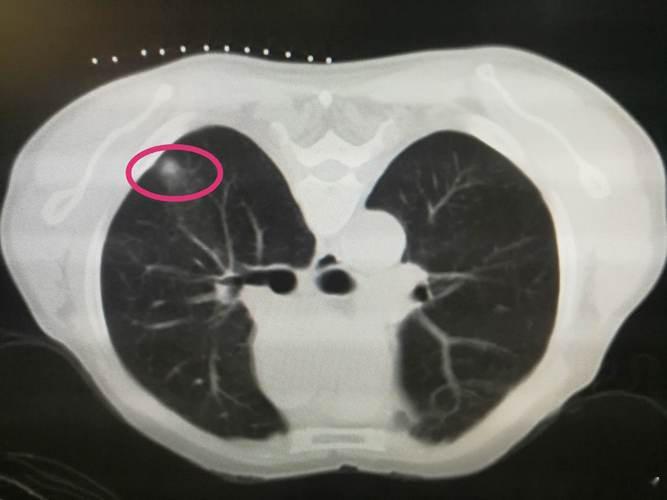

最近很多人拿体检报告来咨询我,肺结节如何调理?

肺结节属于正气不足,痰湿阻塞经络循行、气血不通畅产生结节或淤滞。

中医认为,肺结节的形成多因正气亏虚,痰湿、血瘀积在肺部,气虚、气滞、痰、瘀四者互相影响,导致脏腑功能失调,天长日久积聚而成。中医调理肺结节,一定要因人而异,辨证对待。可以通过使用清肺、润肺、除痰、解郁、软坚、散结的药物、食物,促使肺结节变小,甚至消失。